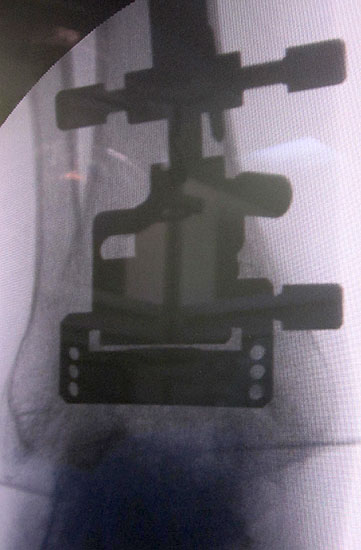

• Prothesenplanung anhand von Röntgenschablonen (Abb. 1 und 2).

• Die Fersen des Patienten sollen mit dem Tischende abschließen (Abb. 3)

• Strahlenschutzmatte; die intraoperative Darstellung des ipsilateralen Hüftgelenkes zur Überprüfung der mechanischen Beinachse (Hüftkopfzentrum/Kniegelenk/ Sprunggelenk) sollte gewährleistet sein